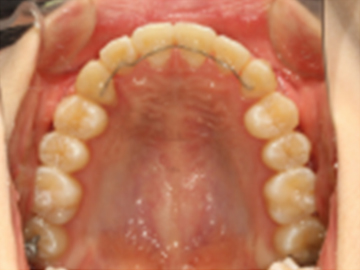

고정식 유지장치를 이용해 교정치료 후 재발을 방지합니다.

가철식 유지장치를 이용해 교정치료 후 재발을 방지합니다.

교정치료 후 일어나는 약간의 재발은 자연스러운 현상 중 하나입니다.

치아와 턱이 생리적으로 가장 편안한 상태를 찾아가면서 일어나기 때문입니다.

하지만, 힘들게 한 교정치료 결과가 다시 예전으로 돌아가는 것은 막아야겠죠!

심다치과에서는 교정치료 후, 위아래 유지장치를 통해 재발이 최소화되고자 합니다.